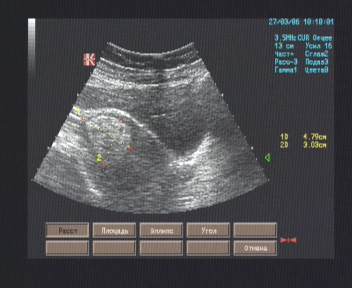

Эхографические признаки фибромиомы (выраженный фиброзный компонент в узле) матки.

Матка 81 х 70 х 48 мм., anteflexio, грушевидной формы, типичного расположения, контуры ровные, миометрий изоэхогенный, неоднородный за счёт гиперэхогенного очага в миометрии верхней половины матки размерами 47 х 38 х 36 мм. с ровными гипоэхогенными границами, однородного внутреннего строения; полость щелевидная, в проекции просвета дополнительных эхоструктур не лоцировано, эндометрий 10 мм. толщиной, изоэхогенный, однородный.

Правый яичник 30 х 19 мм., овальной формы, типичного расположения, контуры ровные, гипоэхогенный, дифференциация слоёв умеренно выражена, в коре 3 фолликула диам. 3 – 7 мм..

Левый яичник полностью прикрыт тенью кишечника.